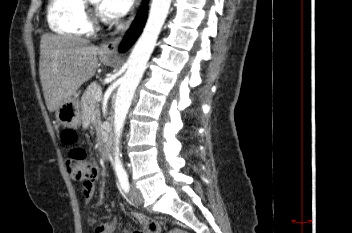

Мультиспиральная компьютерная томография (МСКТ) брюшной полости и забрюшинного пространства относится к современным лучевым методам исследования, с помощью которого можно оценить состояние органов брюшной полости (печени, желчного пузыря, поджелудочной железы, селезенки), забрюшинного пространства с расположенными в нем почками, надпочечниками, мочеточниками и прилегающих к ним кровеносных сосудов и лимфатических узлов.

С помощью мультиспиральной компьютерной томографии проводятся послойные рентгеновские снимки исследуемой области с толщиной среза от 0,5 мм. Затем полученные данные преобразуются в цифровые трехмерные модели органов и систем в мельчайших подробностях.

При подозрении на опухоли, воспалительные процессы, гнойные очаги назначается КТ брюшной полости и забрюшинного пространства с внутривенным болюсным контрастированием. Для этого пациенту внутривенно вводится рентгеноконтрастное вещество на основе йода. Благодаря усиленному кровоснабжению, которое обычно наблюдается в патологических очагах, препарат накапливается в структуре патологических образований и помогает врачу-рентгенологу выявить изменения внутренних органов.

Метод контрастирования помогает максимально точно выявить очаг патологии уже на начальной стадии, а также установить его локализацию, точные размеры, форму и особенности кровоснабжения. Возможности мультиспиральной компьютерной томографии позволяют выполнить своевременную диагностику заболеваний внутренних органов, от чего напрямую зависит эффективность лечения.